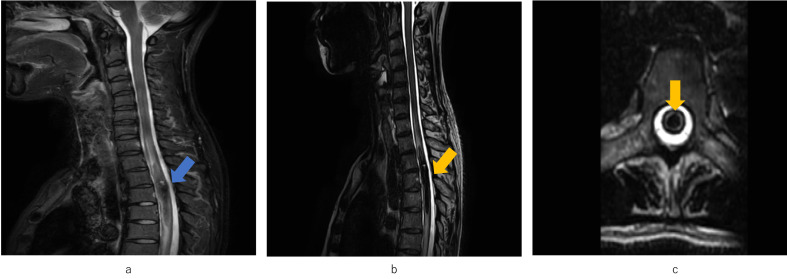

Case: : A woman in her 30s was admitted to the hospital because of the sudden onset of muscle weakness in both lower limbs and cysto-rectal disturbances after COVID-19 infection. She was diagnosed with a hemorrhage from a spinal cord tumor and underwent emergency resection. The pathological diagnosis was a spinal cavernous hemangioma. At first, she had a spinal cord injury (third thoracic vertebrae; American Spinal Injury Association Impairment Scale, C; Frankel classification, B; with cysto-rectal impairment), but 2 months later, she started walking with knee-ankle-foot orthoses and parallel bars. After 3 months, she could move independently around the ward using a wheelchair. Upon discharge, the patient could walk with ankle-foot orthoses and Lofstrand crutches.